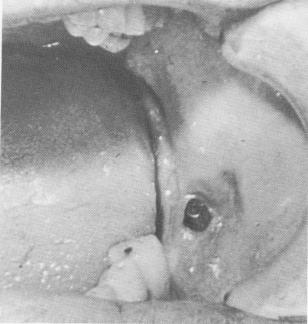

Fig. 4-85. The protruding post of the blade was irritating the patient's cheek because it was originally inserted too far buccally.

4 Buccally protruding post of endosseous blade implant in mandible